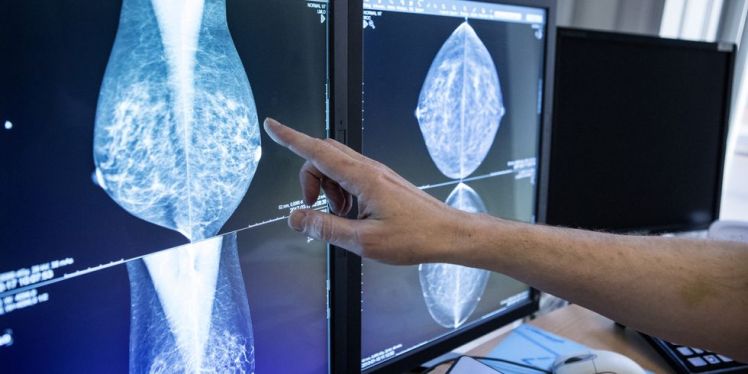

Dense mammary tissue is one of the strongest risk factors for breast cancer and its density also makes it more difficult to detect the cancer. This causes the care to miss every two cases of breast cancer in so-called dense breasts. Now researchers and experts want to customize screening for breast cancer and inform about dense breasts.

Greater risk of cancer in dense breasts – tumors are not visible on mammography

Health care misses every other case of breast cancer in so-called dense breasts. Now scientists and experts want to see changed guidelines and new methods for breast cancer screening. Photo: Christine Olsson / TT